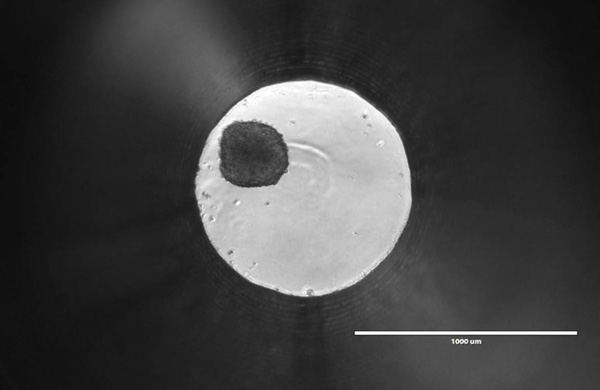

There’s something beautiful about the tiny ball I’m looking at through the microscope. It’s only about 200—250 microns in diameter, smaller than a single grain of salt. As I bump the plate with my finger, the ball rolls around the 1mm well. To me, it may just look like a dark spot within an illuminated circle, but many scientists feel it could represent the future of oncology research and drug discovery.

It’s a Friday afternoon, and I’m staring at a spheroid of roughly 1,000 human liver cells. Promega Research Scientist Mike Valley heard that I was interested in 3-dimensional cell culture models, so he invited me over to his lab in the Research and Development Center to check out the spheroids for myself. Mike is developing a new assay, and with recent trends in cell biology research, he knows it’s crucial to optimize that assay for use with 3D cultures.

Image credits: Spheroid image provided by Insphero, all other photographs by Wesley Bishop.